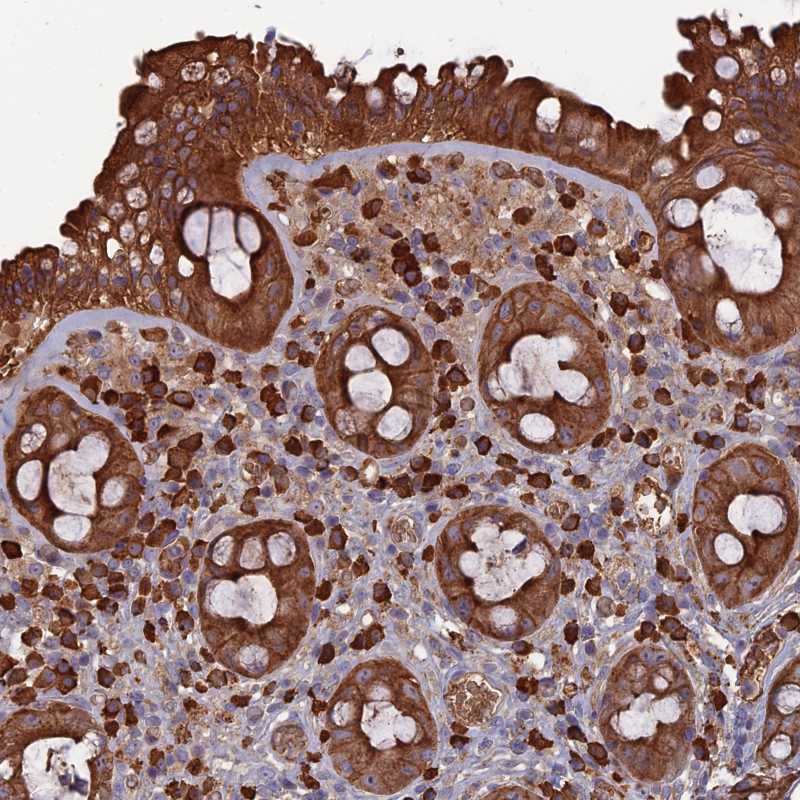

Immunohistochemical staining of human rectum shows strong cytoplasmic positivity in glandular cells.